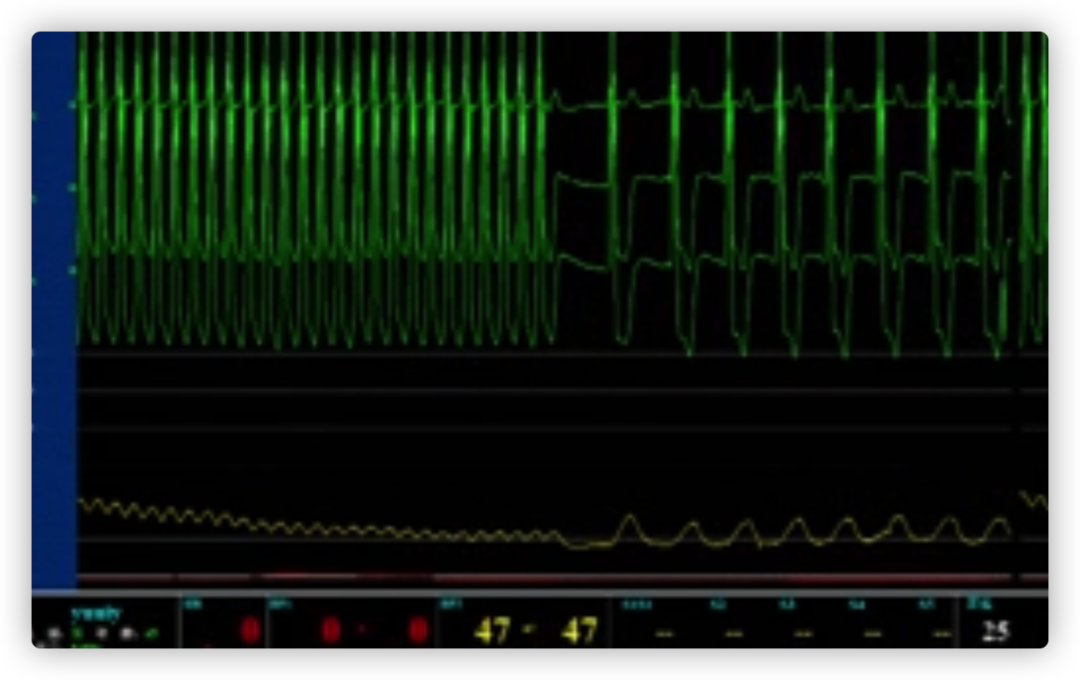

瓣膜内22mm球囊后扩张,左冠无显影

LM烟囱支架植入4.0*30mm

ECG术后即刻